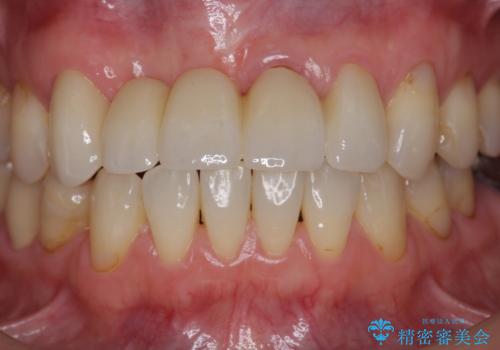

前歯が折れた 前歯部審美セラミックブリッジ治療

- 57万円(仮歯・ファイバーコア・ジルコニアクラウン×5)費用は治療当時の料金となります

かみ合わせの観点からインプラント治療は難しく、入れ歯も希望されなかったためブリッジによる補綴を選択しました。